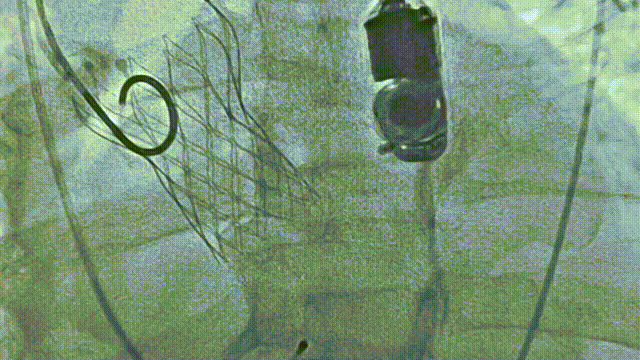

TaurusElite输送系统轻松过弓、跨瓣,AV26瓣膜瓣环下0mm定位释放,到工作位后造影显示瓣膜形态、位置良好,释放脱钩后瓣膜形态、位置良好,冠脉血流灌注正常,无瓣周漏,弓部血管造影未见异常。

工作位评估

释放后造影